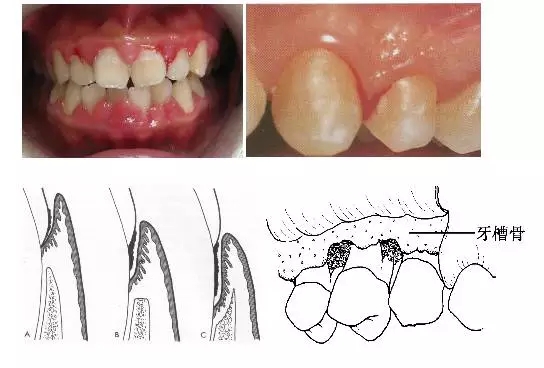

1、牙齦改變:正常牙齦粉紅色、菲薄而緊貼牙面,附著齦有點(diǎn)彩。患牙齦炎時(shí)游離齦和齦乳頭呈鮮紅或暗紅色,齦緣變厚,齦乳頭圓鈍,不再緊貼牙面;由于結(jié)締組織內(nèi)炎性浸潤(rùn)及膠原纖維消失,使原來(lái)致密堅(jiān)韌的牙齦變得松軟脆弱,缺乏彈性;同時(shí)由于牙齦腫脹或增生,齦溝深度增加,但上皮附著水平仍位于正常的釉牙骨質(zhì)界,即出現(xiàn)假牙周袋。

3、牙周袋形成:牙周袋是病理性加深的齦溝,是牙周炎最重要的病理改變之一。按照袋底的位置,可將牙周袋分為骨上袋和骨下袋;按牙周袋累及牙面的情況可將其分為單面袋、復(fù)合袋、復(fù)雜袋。

4、牙槽骨吸收:牙槽骨吸收是牙周炎的另一個(gè)主要病理變化,由于牙槽骨的吸收,使牙齒的支持組織喪失,牙齒逐漸松動(dòng),最終脫落或拔除。牙槽骨的吸收可分為水平吸收、垂直吸收、凹坑狀吸收等幾種類(lèi)型。

5、牙齒松動(dòng)和移位:由于牙周炎使牙槽骨吸收,牙周支持組織減少是牙齒松動(dòng)的最主要原因;另外在咬頜創(chuàng)傷合并有牙周炎時(shí),也可造成牙齒松動(dòng)。由于患有牙周炎的牙齒缺乏牙周支持組織,所以,在咬頜創(chuàng)傷的不良咬頜力作用下,牙齒可出現(xiàn)病理性移位。